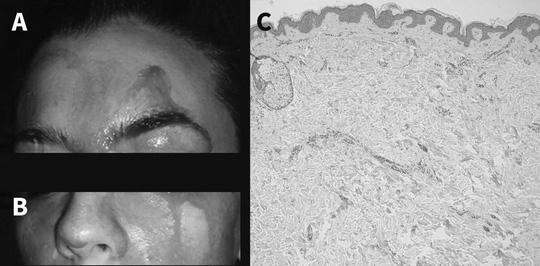

Các bác sĩ đã chẩn đoán cô thực sự bị chảy máu cam do hiện tượng các mao mạch dưới da vỡ ra và thấm qua những vùng da hoàn toàn lành lặn. Một vài loại thuốc hướng thần được kê toa cho bệnh nhân, nhằm chống trầm cảm và giúp tâm trạng cô tốt hơn. Hiện tượng chảy máu có giảm nhưng vẫn không dừng lại.

Bệnh nhân được phát hiện có triệu chứng xơ vữa động mạch khá rõ ràng, huyết áp không ổn định. Các chuyên gia cho rằng những điều này và hiện tượng chảy máu qua da có liên quan.